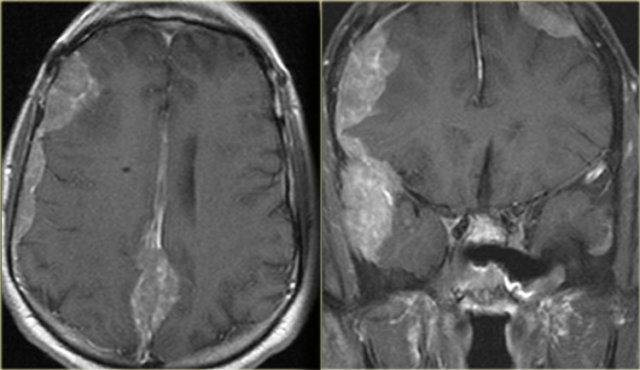

Hình ảnh bên trái của một bệnh nhân ban đầu được chẩn đoán là u nguyên bào thần kinh đệm đa dạng (glioblastoma multiforme).

Có các bất thường ở cả hai thùy trán.

Tuy nhiên, hãy chú ý đến mô bất thường trong xoang trán (mũi tên vàng), áp xe dưới màng xương (mũi tên đỏ) và mức dịch-dịch (mũi tên xanh lá) trong tổn thương nội sọ lớn có hình ảnh ngấm thuốc dạng vòng nhẫn.

Tất cả các bất thường liên tục với nhau, cho thấy có sự phá hủy xương trán.

Hình ảnh khuếch tán hạn chế cũng hỗ trợ chẩn đoán áp xe não.

Đây là áp xe dưới màng xương và viêm tủy xương của xương trán, thường kèm theo sưng nề mềm và đau vùng trán.

Tình trạng này còn được gọi là khối u phồng Pott (Pott’s puffy tumor) theo tên Sir Pott, một phẫu thuật viên người Anh, người đầu tiên mô tả thực thể bệnh lý này.